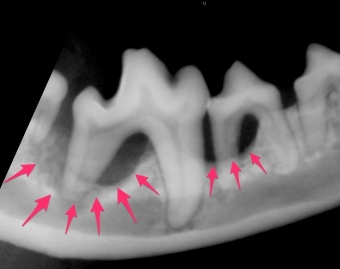

たとえばこの写真わんこは、外見は歯石以外には大きな異常はありませんでした。しかしレントゲンを撮影すると、この写真の矢印の部分が重度の歯周病であごの骨が溶けていることがわかります。このまま歯石を取るだけではなんの解決にもならず、場合によってはもっと骨が溶けて顎の骨が骨折ということも起こりえます。ここまで骨が吸収された歯は抜歯が必要になります。確かに抜歯は可哀想かもしれませんが、もし抜歯をせずに置いておけば、動物の不快感は取れず、将来もっと大変な問題を起こしてしまします。